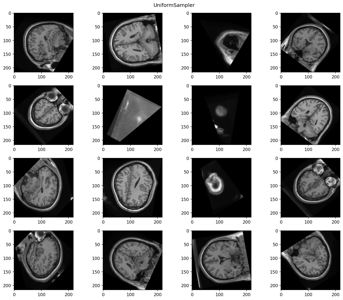

Sometimes we would like to see which transform was applied to a certain batch